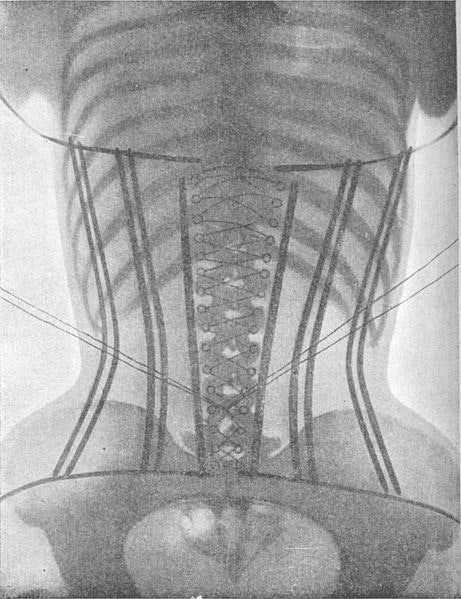

Pero miremos de nuevo a la época final de auge del corsé, antes de 1914. Aquí es donde entran en juego los rayos X que menciono en el título del post. El uso del corsé estaba tan extendido, y tantas veces se llevaba a extremos tan peligrosos, que un médico francés que atendía al nombre de Ludovic O’Followell, publicó todo un tratado médico acerca de esta prenda de vestir.

Su objetivo era el dar a conocer todos los detalles acerca de cómo se podía utilizar el corsé con fines médicos, estéticos pero, también, mostrar cómo podía llegar a modificar la morfología femenina y hasta la fisiología normal. Se ha dicho muchas veces que el trabajo con rayos X sobre mujeres con corsé que llevó a cabo Ludovic O’Followell estaba destinado a denunciar las patologías originadas por el mal uso de la prenda. A lo largo del tratado Le Corset, que contó con una edición en 1905 y una ampliación en 1908, se mencionan los peligros de ciertos usos del corsé, pero también se ensalza su empleo cuidadoso. Además, cabe recordar que este médico era columnista de la revista de moda Les Dessous Elegance. Las siguientes imágenes pertenecen a su tratado sobre el corsé y hablan por sí mismas.